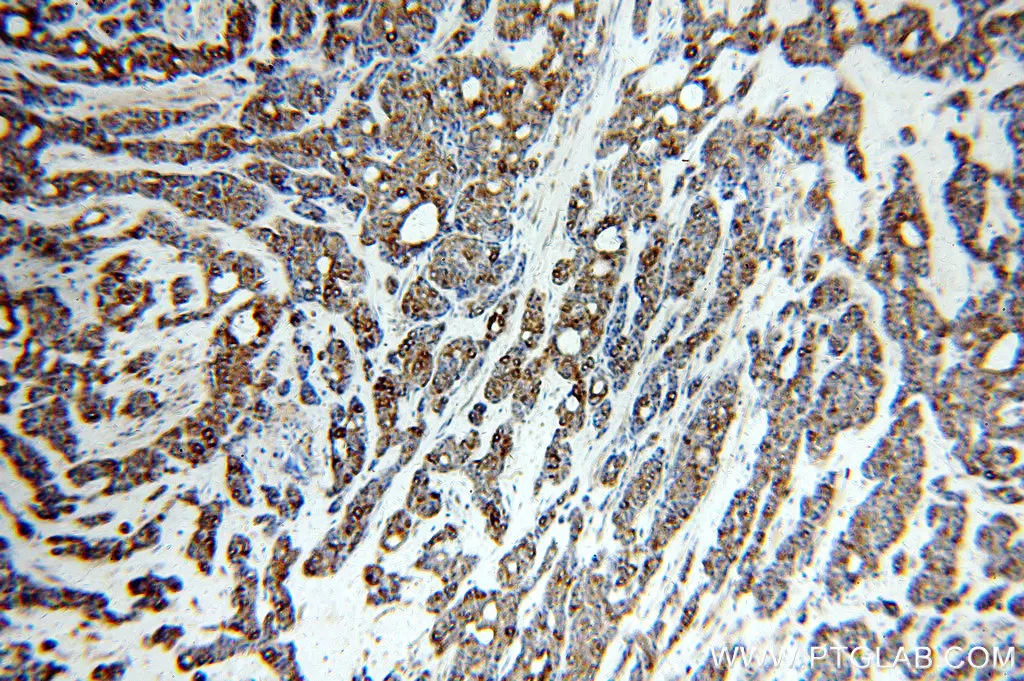

Immunohistochemical analysis of paraffin-embedded human cervical cancer using 10883-1-AP (p16INK4a antibody) at dilution of 1:2000 (under 10x lens).